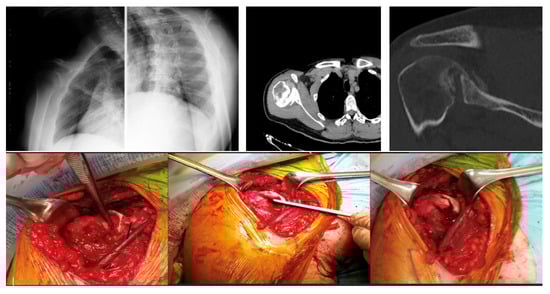

We therefore have the following four types of confirmed posterior fracture dislocation (Figure 1):

Type 1: chronic posterior dislocation is associated with humeral bone deficit ranging from 20% to 50% of the extension of the articular surface; it is the most frequent type;

Type 2: the deficit is greater than 50%;

Type 3: fracture dislocation of the humeral head, in which the continuity between the humeral head and the diaphysis is ensured by a posterior bony portion which acts as a hinge between the two structures. The fracture can be localized at the anatomical neck level, or it can involve a medial portion of the diaphysis. The articular pro-file of the humeral head is preserved.

Type 4: the fracture is multi-fragmentary with complete subversion of the profile of the articular surface [4].

Figure 1. Classification of chronic posterior shoulder dislocation and fracture dislocation. Type 1 (A) humeral bone deficiency extending from 20 to 50% of the articular surface of the humeral head; Type 2 (B) humeral bone deficiency extending to more than 50% of the articular surface of the humeral head; Type 3 (C) fracture dislocation of the humeral head in the absence of bone deficiency. Type 4 (D) fracture dislocation with multifragmentation of the humeral head.